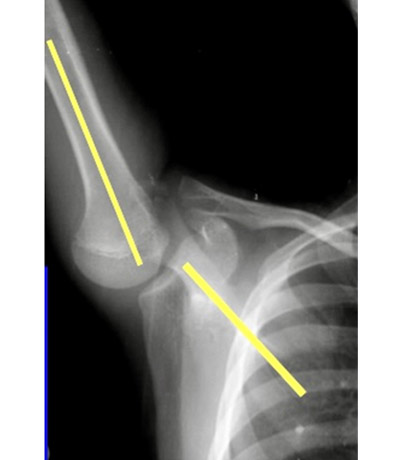

10代男児(野球の投球にて右肩の痛み)

※上腕骨の回旋ストレスを無くす特殊な姿勢で撮影

異常

上腕骨と肩甲骨の肩甲棘のバランス(肩甲上腕リズム)の乱れ

肩甲骨周囲の筋力・柔軟性の低下による機能不全から起こった痛みと診断